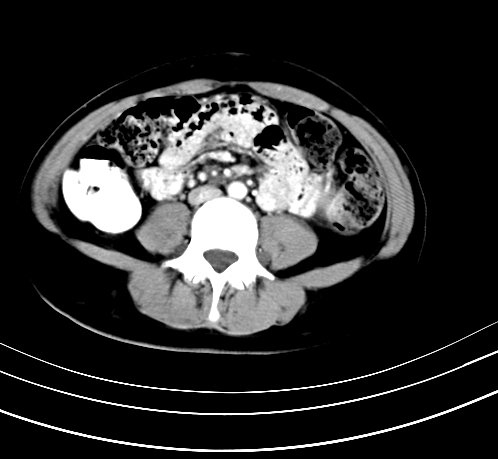

腹部平扫

动脉期